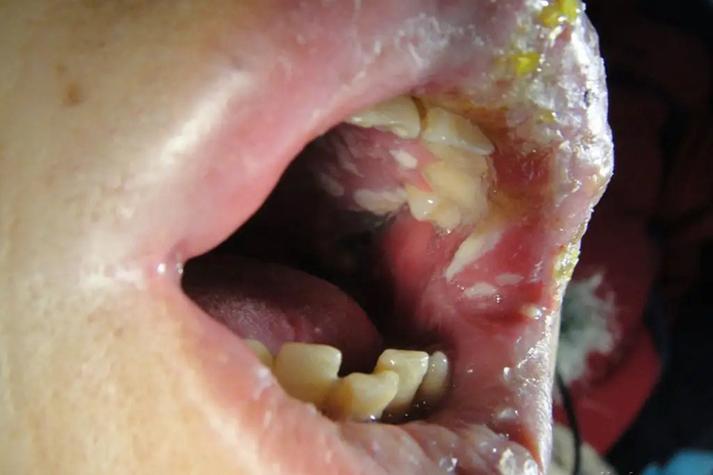

- 天疱疮: 这是一种比较严重的自身免疫性疾病,非常罕见,典型特征是口腔和皮肤上出现松弛的、易破的水疱,疱壁很薄,破溃后形成大面积的、不易愈合的糜烂面,疼痛剧烈,如果您怀疑是这个,请务必立即就医。